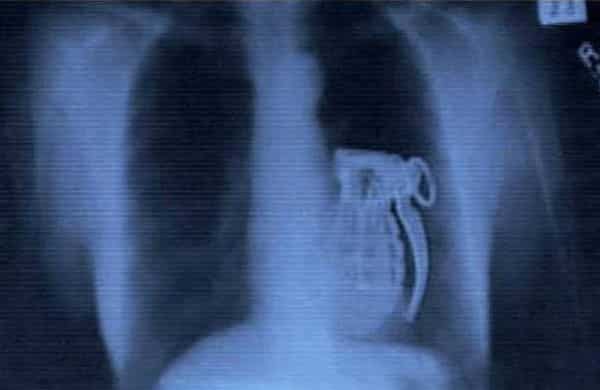

3. Une grenade

Être une bombe.